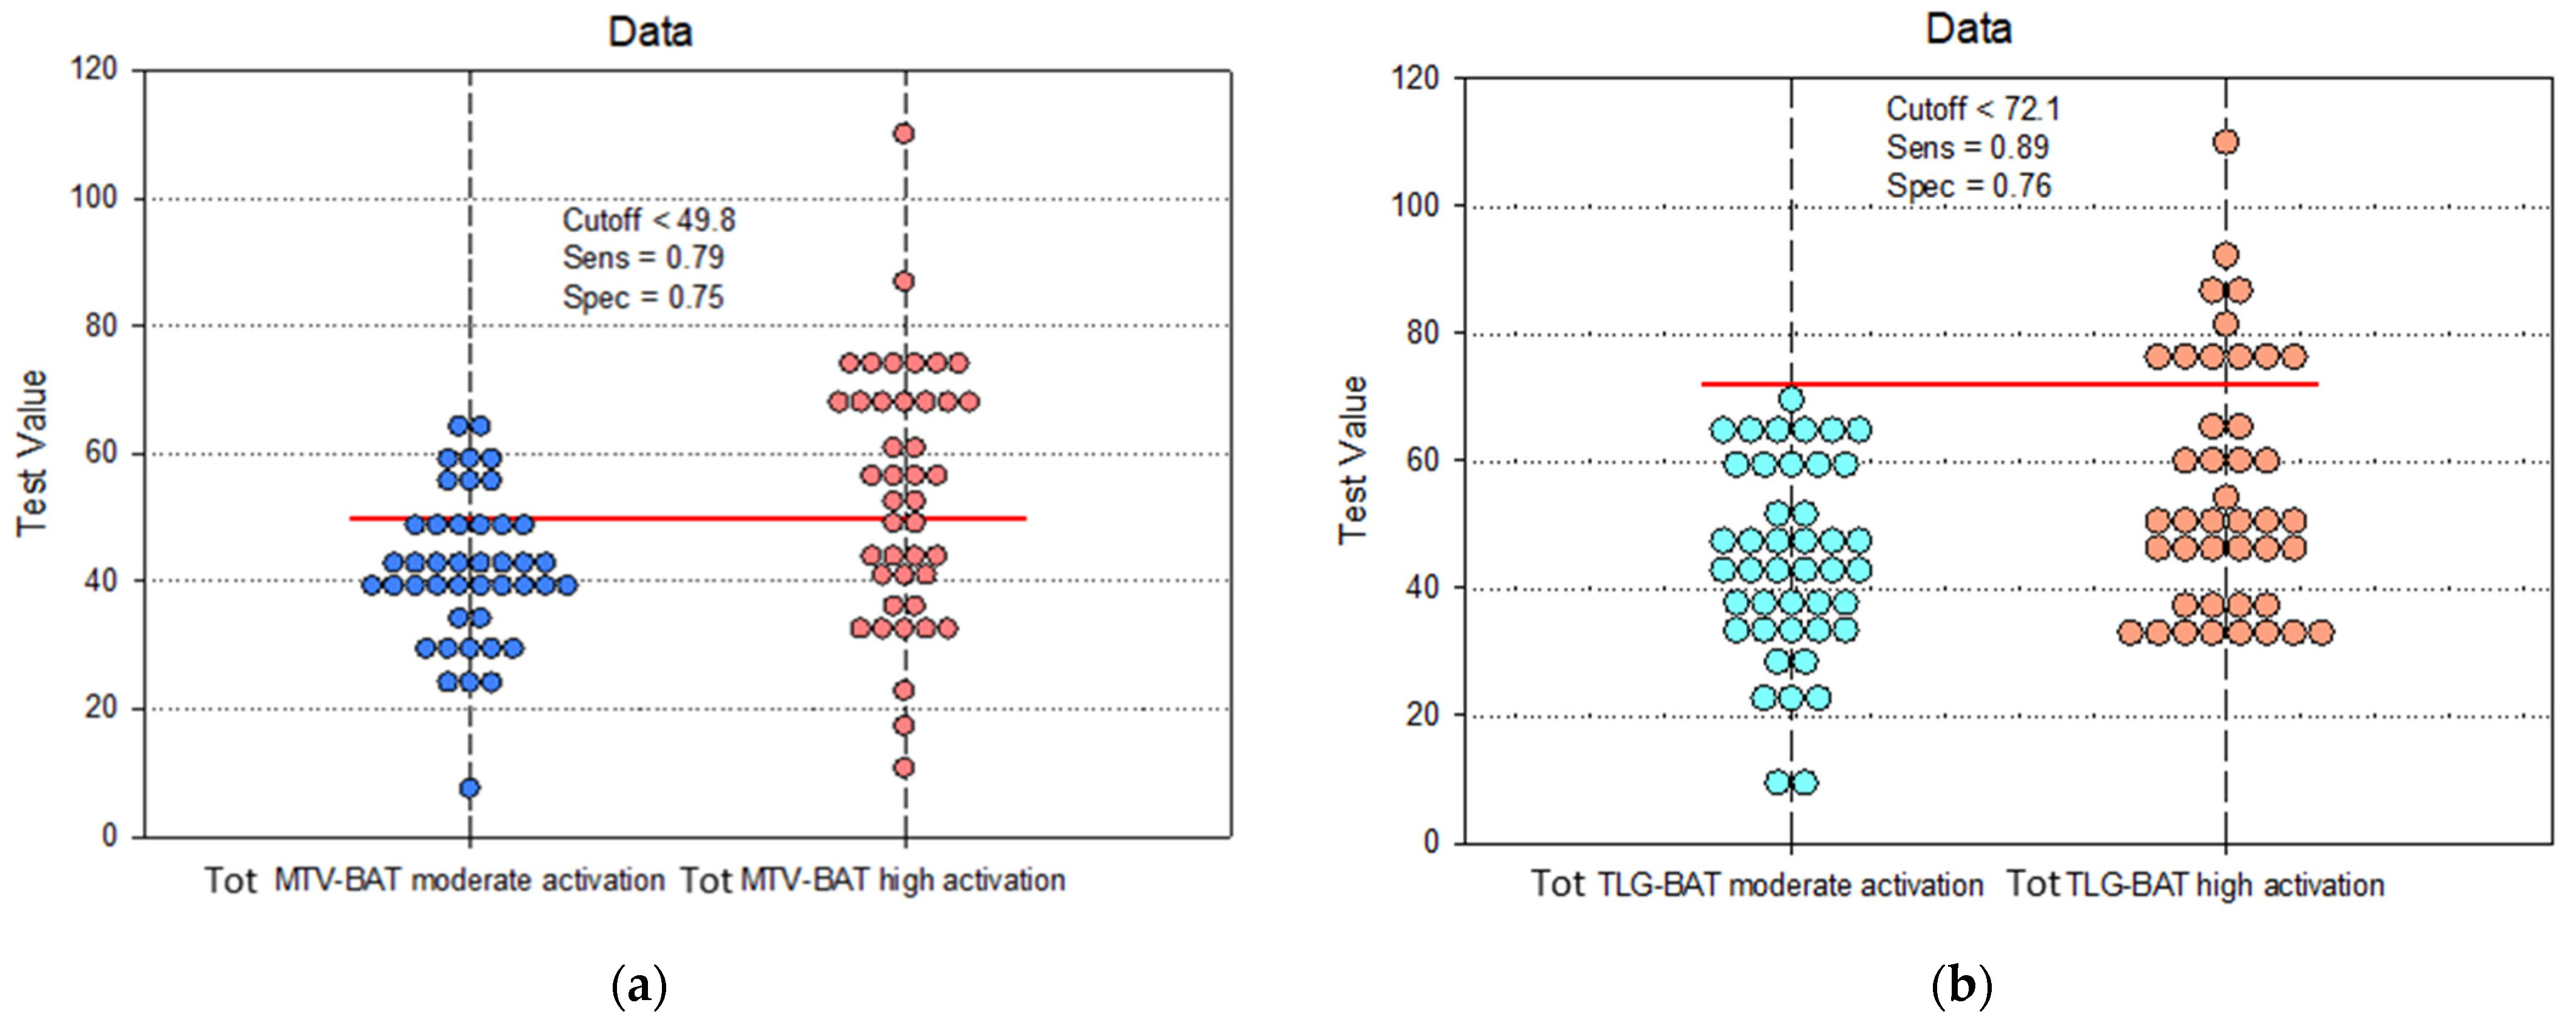

| Sensitivity | 95% CI | Specificity | 95% CI | PPV | NPV | Cutoff | |

|---|---|---|---|---|---|---|---|

| Tot MTV | 0.79 | 0.67 to 0.91 | 0.75 | 0.69 to 0.87 | 0.85 | 0.83 | 49.8 |

| Tot TLG | 0.89 | 0.71 to 0.92 | 0.76 | 0.68 to 0.94 | 0.73 | 0.87 | 72.1 |